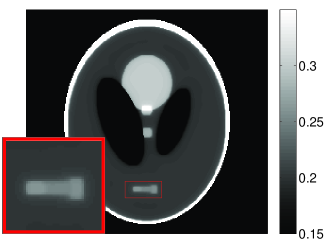

• [63] C. W. Dodge, A rapid method for the simulation of filtered X-ray spectra in diagnostic imaging systems (ProQuest, 2008).